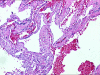

Case presentation: A 27 year male presented with a gradually enlarging, asymptomatic swelling on left supraclavicular region with normal overlying skin. A soft mass, about 7 x 7 cm with restricted mobility was found with normal cranial nerve function. Fine needle aspiration cytology showed a hemorrhagic aspirate. Doppler showed a mass displacing left carotid artery posteriorly while left internal jugular vein was not visualized. Magnetic resonance imaging showed a well defined mass isointense to hypointense on T1 weighted and hyperintense on T2 weighted and STIR images with fluid-fluid levels. On exploration, a vascular mass arising from left internal jugular vein was found with good tissue planes, which was excised after ligating the patent internal jugular vein above and below the lesion. Histopathologic examination confirmed the diagnosis of vascular malformation.